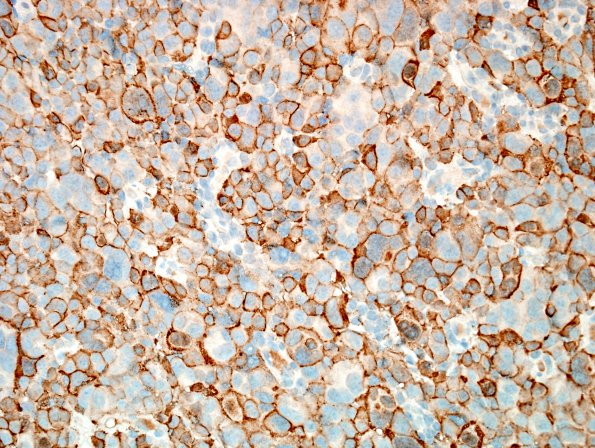

3B Pituitary Carcinoma, metastatic (Case 3) ACTH 1.jpg

The tumor is a pituitary carcinoma, corticotroph subtype. (ACTH IHC)